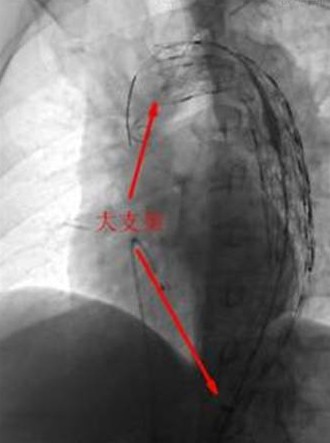

12月2日上午10時(shí),完善各項(xiàng)術(shù)前準(zhǔn)備工作后,患者被送進(jìn)了介入診療中心手術(shù)室。心血管醫(yī)學(xué)中心的專家們迅速為患者實(shí)施了主動脈造影術(shù),發(fā)現(xiàn)患者撕裂的主動脈竟有兩個(gè)破口!如果不封住這兩個(gè)破口,血流將會從破口不斷流入撕裂的假腔并導(dǎo)致假腔內(nèi)壓力越來越大,而當(dāng)假腔的壓力達(dá)到一定程度后就有可能完全破裂而導(dǎo)致大出血死亡。因此,如何封住這兩個(gè)破口就成了挽救該患者生命的主要目標(biāo)。以前完成此目標(biāo)必須進(jìn)行開胸手術(shù),將一種人造的血管縫合在夾層的內(nèi)表面從而堵住破口。而心血管醫(yī)學(xué)中心的專家們采用當(dāng)今最先進(jìn)的技術(shù),甚至不需股動脈切開,僅僅在大腿根部的股動脈打一個(gè)小孔即完成了這一高難度的手術(shù)!他們通過這一小孔建立了一個(gè)輸送通道,并順著這一通道先后將兩個(gè)大覆膜支架由遠(yuǎn)及近釋放到患者撕裂的主動脈內(nèi),并牢牢地封住了兩個(gè)撕裂的破口,整個(gè)手術(shù)過程不到2個(gè)小時(shí)!該手術(shù)的成功,標(biāo)志著我市心臟大血管疾病的診療技術(shù)水平又邁上了一個(gè)新的臺階!